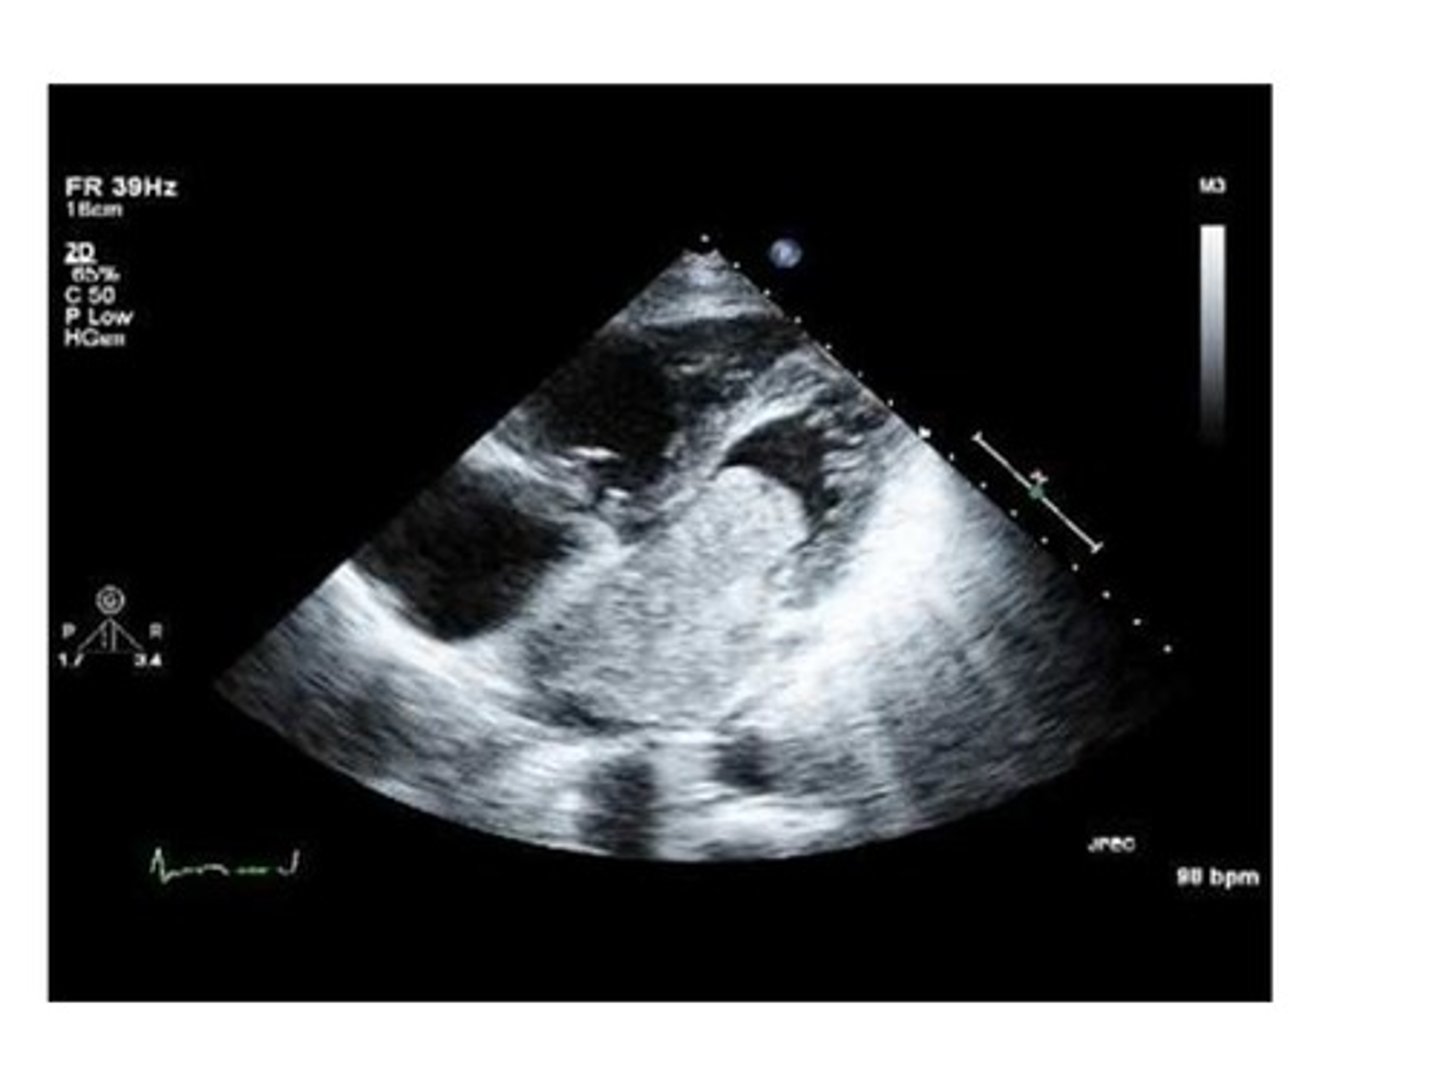

If the the heart is unable to pump sufficient blood to meet the metabolic needs of the body, view the image and predict what the pathology might be.

angina pectoris

CHF (congestive heart failure)

myocardial infarction

arrhythmias

Reviewing the image, the left ventricle has a bulge in the apex which could have been caused by a myocardial infarction. The bulge in the apex is known as:

thrombus

aneurysm

clot

stenosis

A bulge in the left ventricle along with the thinning of necrotic tissue of the infarcted wall and the high pressure in the ventricle during ejection may cause which of the following?

rupture

regurgitation

nothing is at risk of happening